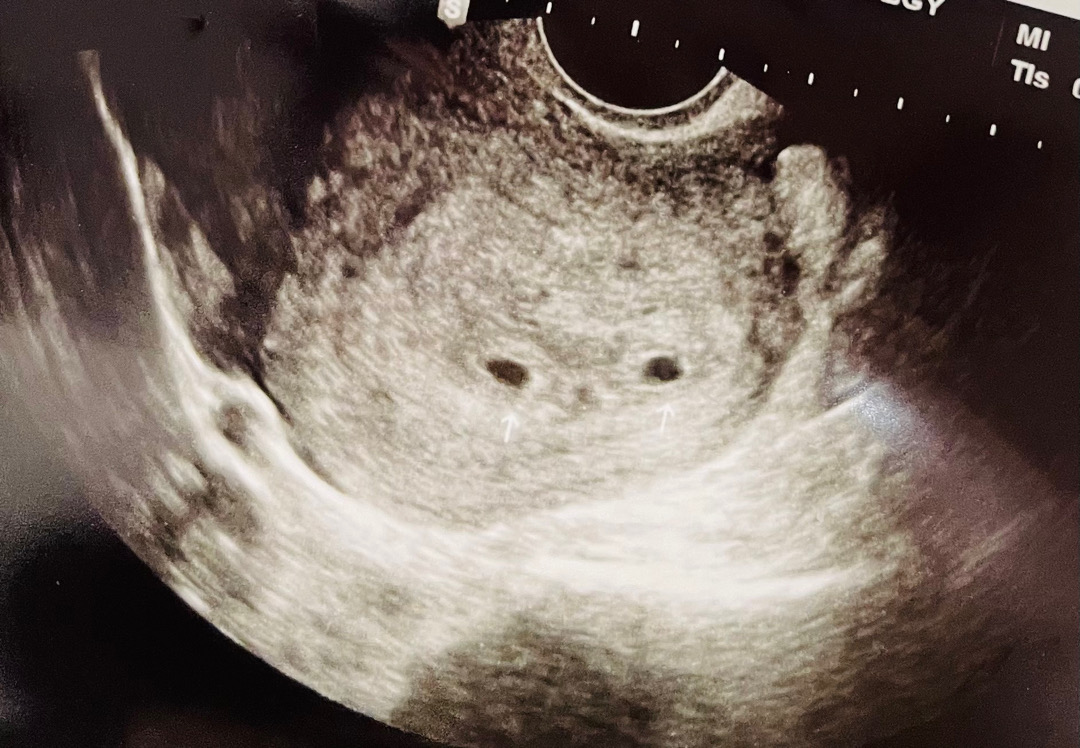

첫 초음파 보고왔는데..

5주 0일차 첫 초음파 보고왔는데 아기집같은게 두개라고... 아직 초기라 확실치않아 애매하긴한데 하나가 피비침이나 틈새라기에는 모양이 너무 두개다 동그랗다고 쌍둥이일 확률이 높아보인다규 하시네요,,, 크기도 0.44 0.47 이네요... 담주에 다시 초음파 보자고 하시는데 쌍둥이로 보이시나요?ㅎㅎㅎ 하하하 쌍둥이는 상상도 못해 당황스럽네요;;